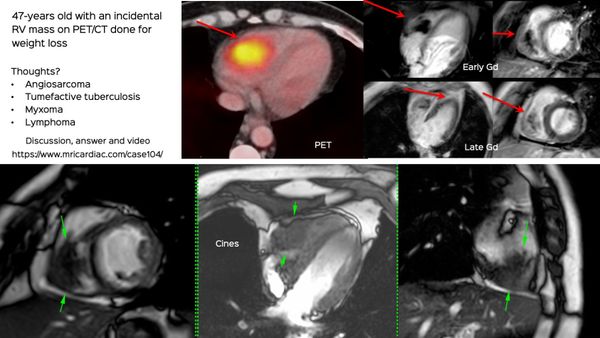

Sometimes, the heart is just one of the organs involved and a cardiac MRI or CT can start a cascade leading to the final diagnosis.